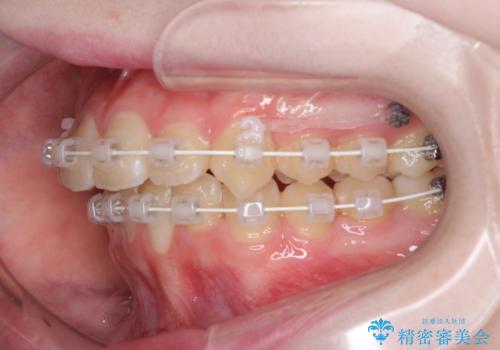

- 矯正装置

- 審美装置

インビザラインでの自己管理は難しいとのことで、ワイヤー装置にて矯正を行うこととしました。